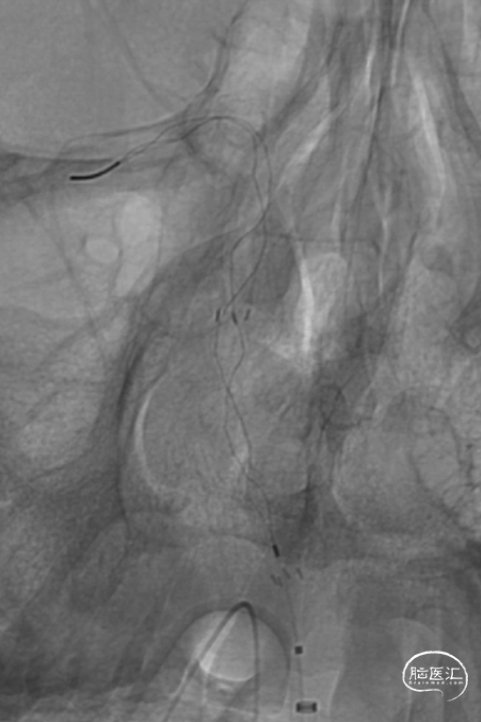

释放加奇4.0mm*30mm Syphonet®取栓支架,可见支架通体显影。

交换再次引入加奇4.0mm*30mm Syphonet®取栓支架并释放。

基底动脉支架内再狭窄导致的闭塞取栓风险高,操作复杂,Syphonet®取栓支架通体显影,可以清楚看见取栓支架与基底动脉内原有支架的关联,避免支架移位,提高手术安全。